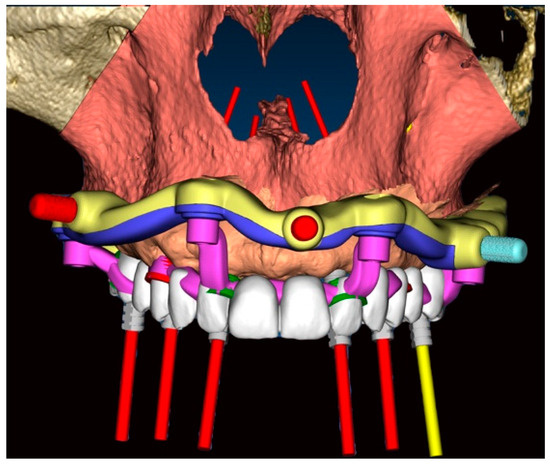

- 16: Oxy Implant FIXO Short 30° 4 × 10 mm

- 14: Oxy Implant FIXO Short 17° 4 × 10 mm

- 12: Oxy Implant FIXO Mini 17° 3.5 × 11.5 mm

- 22: Oxy Implant FIXO Mini 17° 3.5 × 13 mm

- 24: Oxy Implant FIXO Short 17° 4 × 11.5 mm

- 26: Oxy Implant FIXO Short 17° 4 × 8.5 mm

- Fixed component or base template: printed resin (Clear MED610™; Stratasys, Edina, MN, USA), reinforced with milled titanium grade 5 (SINERGIA DISK Ti; Nobil Metal, Bergamo, Italy).

- Removable components, screwed to the base template, consisting of:

- Positioning template: printed resin (Clear MED610™; Stratasys, Edina, MN, USA);

- Implant placement template (Figure 7): milled titanium grade 5 (SINERGIA DISK Ti; Nobil Metal, Bergamo, Italy);

- Provisional prosthesis: milled PMMA (Multilayer PMMA Disc; Dentsply Sirona, Verona, Italy) and a milled titanium grade 5 core (SINERGIA DISK Ti; Nobil Metal, Bergamo, Italy.